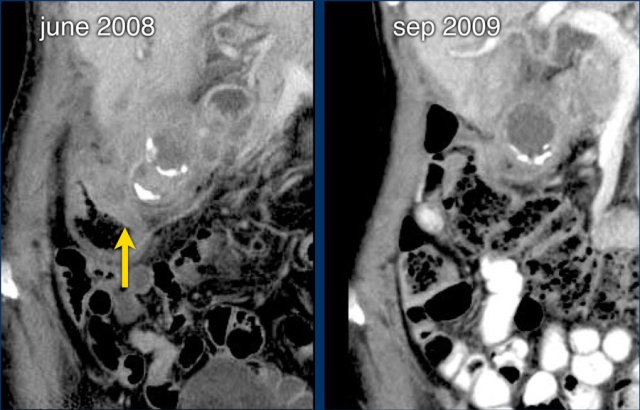

In june 2009 this patient presented with longstanding cholecystitis with two large stones.

Severe local colonic wall thickening with small intramural abscesses reflect the impending fistulisation process.

The patient was treated conservatively and in september 2009 she was symptomfree.

One of the stones and the pus had evacuated to the colon.

Two years later, also the second stone did evacuate subclinically.

A persistent open fistulous tract between gallbladder and right colon was demonstrated on CT and at ERCP.

On CT the tract is seen (yellow arrow) and there is air in the galbladder.

On ERCP the contrast is injected in the bile ducts and fills the gallbladder through the cystic duct and finally also the right colon.